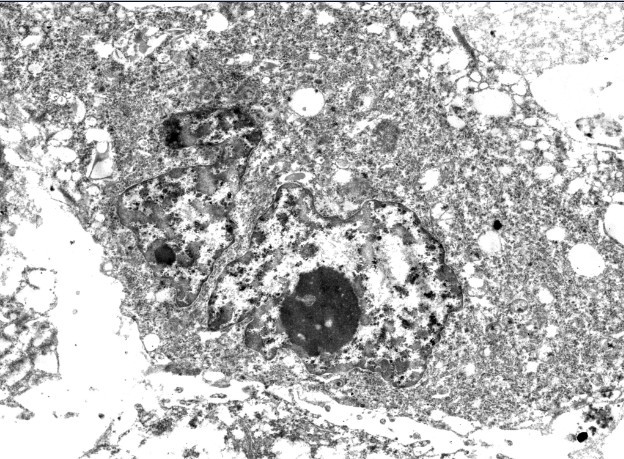

快来看快来瞧 我的细胞电镜照片~~

上传处理前和处理后的细胞照片,虫友们帮我看看处理后细胞成这样,都可能是什么原因啊?

处理前:

处理后:

处理后理论上不能有太大变化,这结果是不是因为没固定好?细胞凋亡?还是什么可能性?

请电镜图片分析高手指点。